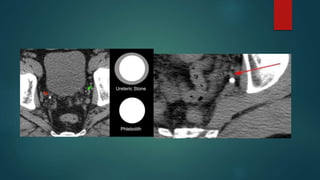

Ct

 In patients with little retroperitoneal fat, distinguishing a ureteric calculus

from a phlebolith can be challenging. Two signs have been found

helpful 12:

 comet-tail sign - favours a phlebolith

 soft-tissue rim sign - favours a ureteric calculus

 comet-tail sign :The sign refers to a tail of soft tissue extending from a

calcification, representing the collapsed/scarred/thrombosed parent

vein. When well seen it is said to have a positive predictive value of

100% 1.

 The soft-tissue rim sign is used to distinguish a ureteric calculus from

a phlebolith. The former appears as a calcific density with a surrounding

rim of soft tissue which represents the oedematous ureteric wall.

Phleboliths on the other hand usually have imperceptible walls

(although up to 8% may have a soft tissue rim sign 2) but may have

a comet-tail sign.